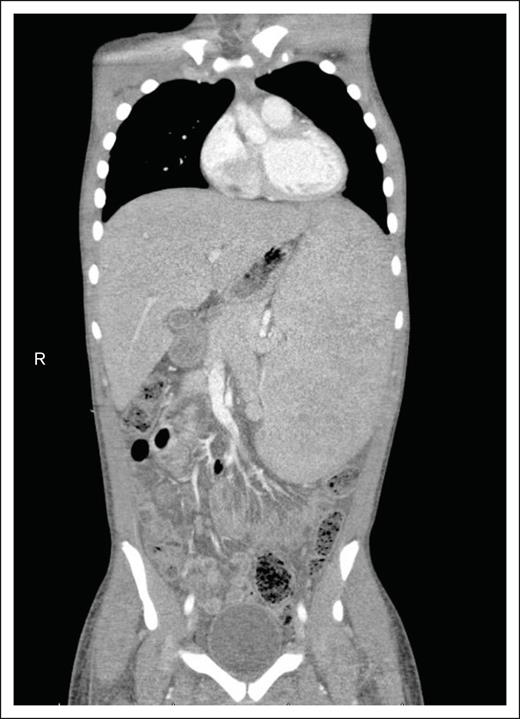

In terms of imaging, contrast-enhanced CT and PET/CT scans are commonly used to evaluate whole-body metabolic and morphologic presence of disease, similar to children and adolescents with other NHL (Figure 2).68 Use of magnetic resonance imaging (MRI) and PET/MRI have also been described; however, similar to other lymphomas, they are recommended as alternative or adjunctive imaging modalities due to the superior sensitivity and specificity of CT and CT/PET in detecting both nodal and extranodal disease.69,70 CT and PET/CT each have pros and cons.71 CT scans can miss extranodal disease, particularly relevant for HSTCL. PET/CT scans have not been studied as extensively in pediatric NHL compared with adults and other malignancies and may be inadequate for response assessment alone.72,73 CTs usually show an enlarged liver and spleen without discrete lesions, whereas PET/CT may show avidity in the liver, spleen, and bone marrow.71,74

Imaging findings in HSTCL. CT scans of the abdomen and pelvis typically reveal massive hepatosplenomegaly, displacing other organs, with minimal enlarged lymph nodes. R, right side of the body.

Imaging alone is insufficient for evaluation. Bilateral bone marrow aspirates and biopsies are essential for staging because bone marrow involvement is common.45 Additional biopsies of the spleen or liver may be needed, based on examination, imaging, and histopathologic findings. Central nervous system involvement has not been described in pediatric HSTCL. To our knowledge, there has been 1 case report of this phenomenon reported in a 41-year-old woman with a cortical mass.75 Therefore, we do not routinely recommend head imaging or lumbar puncture with cerebrospinal fluid examination unless clinically indicated.